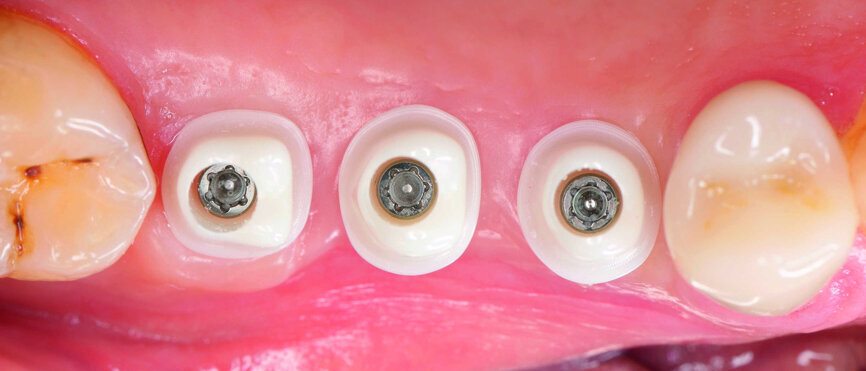

Fig. 19 : Vue latérale des coiffes d’empreinte.

Les implants et la morphologie de la mâchoire ont été moulés pour la fabrication des piliers individualisés en zircone. La prise d’empreintes en technique à ciel ouvert a requis le dévissage des façonneurs gingivaux, de façon à permettre la mise en place de coiffes d’empreinte en PEEK. Une certaine expérience est nécessaire pour vérifier la précision de l’ajustement sur la radiographie de contrôle, car seule la périphérie du matériau est radio-opaque (Figs. 19 et 20).